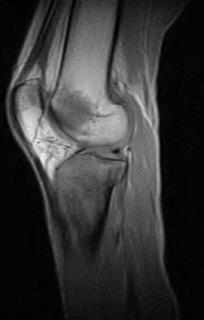

2.jpeg

侧位片

右胫骨上三分之一骨骺及干骺端可见混合性溶骨-硬化性病变,部分区域呈浸润性改变,并可见较宽的过渡带。

未见皮质破坏或骨膜反应。